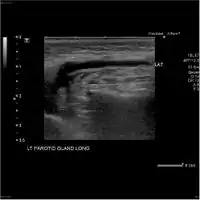

Acute left parotid sialadenitis